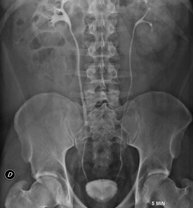

- RX Abdomen

Tècnica que usa els raigs X a través de la qual s'obtenen imatges de l'abdomen (estómac, intestí prim, intestí gros, fetge, ronyons, bufeta, pelvis òssia, etc.) per al seu estudi. - RX Columna lumbar

- UIV (Pielografia descendent)

La urografia intravenosa (UIV) consisteix en l'obtenció d'imatges radiològiques seriades del ronyó, vies urinàries i bufeta. Aquest estudi requereix sempre l'ús d'un contrast iodat. - Cistografía (CUMS)